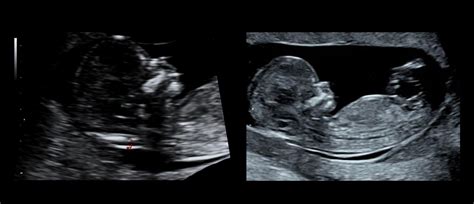

Sodobna ultrazvočna in laboratorijska diagnostika ter povečana ozaveščenost žensk omogočajo zgodnje odkrivanje večine nepravilnosti v zgodnji nosečnosti, še preden bi prišlo do obsežnejših krvavitev, ki bi ogrozile življenje nosečnice in zahtevale transfuzijo krvi. Zelo pomembno je tudi preprečevanje imunizacije RhD-negativnih nosečnic.